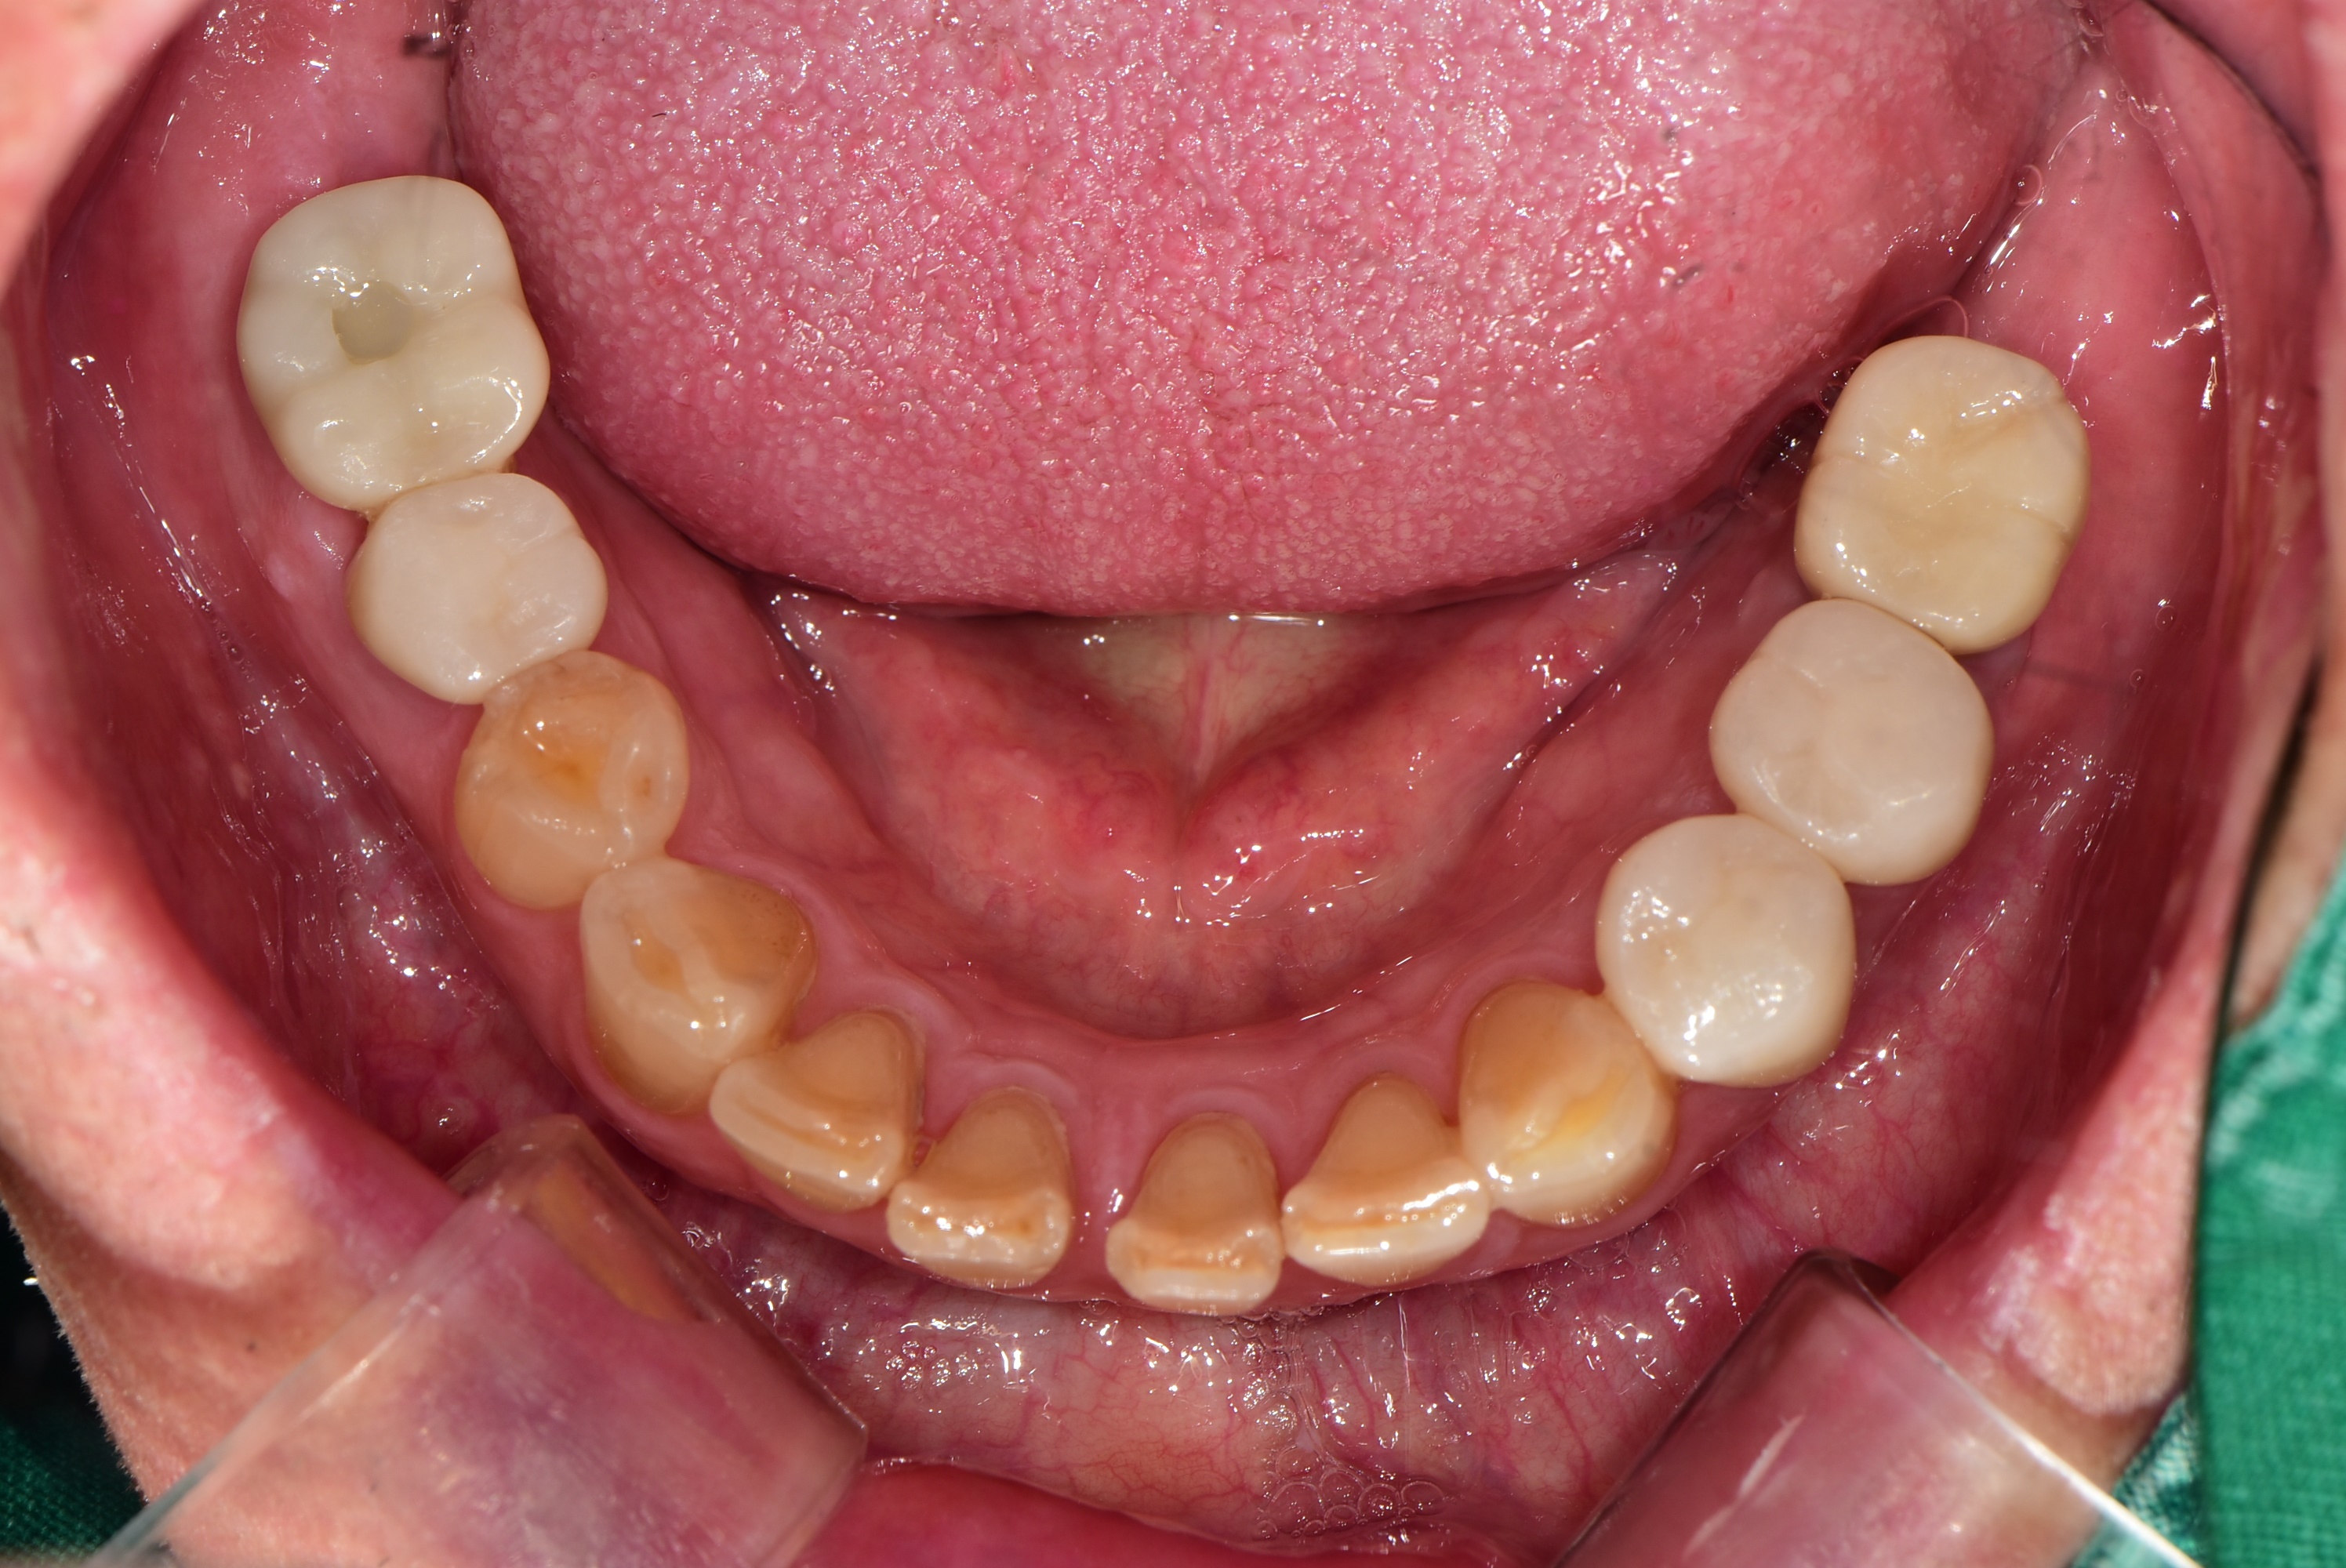

김포 서울케이치과에서 진행한 어금니 다수치아 임플란트 사례입니다.

심한 충치로 인하여 뿌리만 남은 어금니로 인하여 식사가 불편하셨던 50대 남성 환자분이 소개로 내원하셨습니다.

경제적인 이유로 첫번째 어금니까지만 임플란트를 식립하셨고, 6개의 작은 어금니는 심한 파절과 마모로 크라운 치료를 하였습니다.

<치료 후>